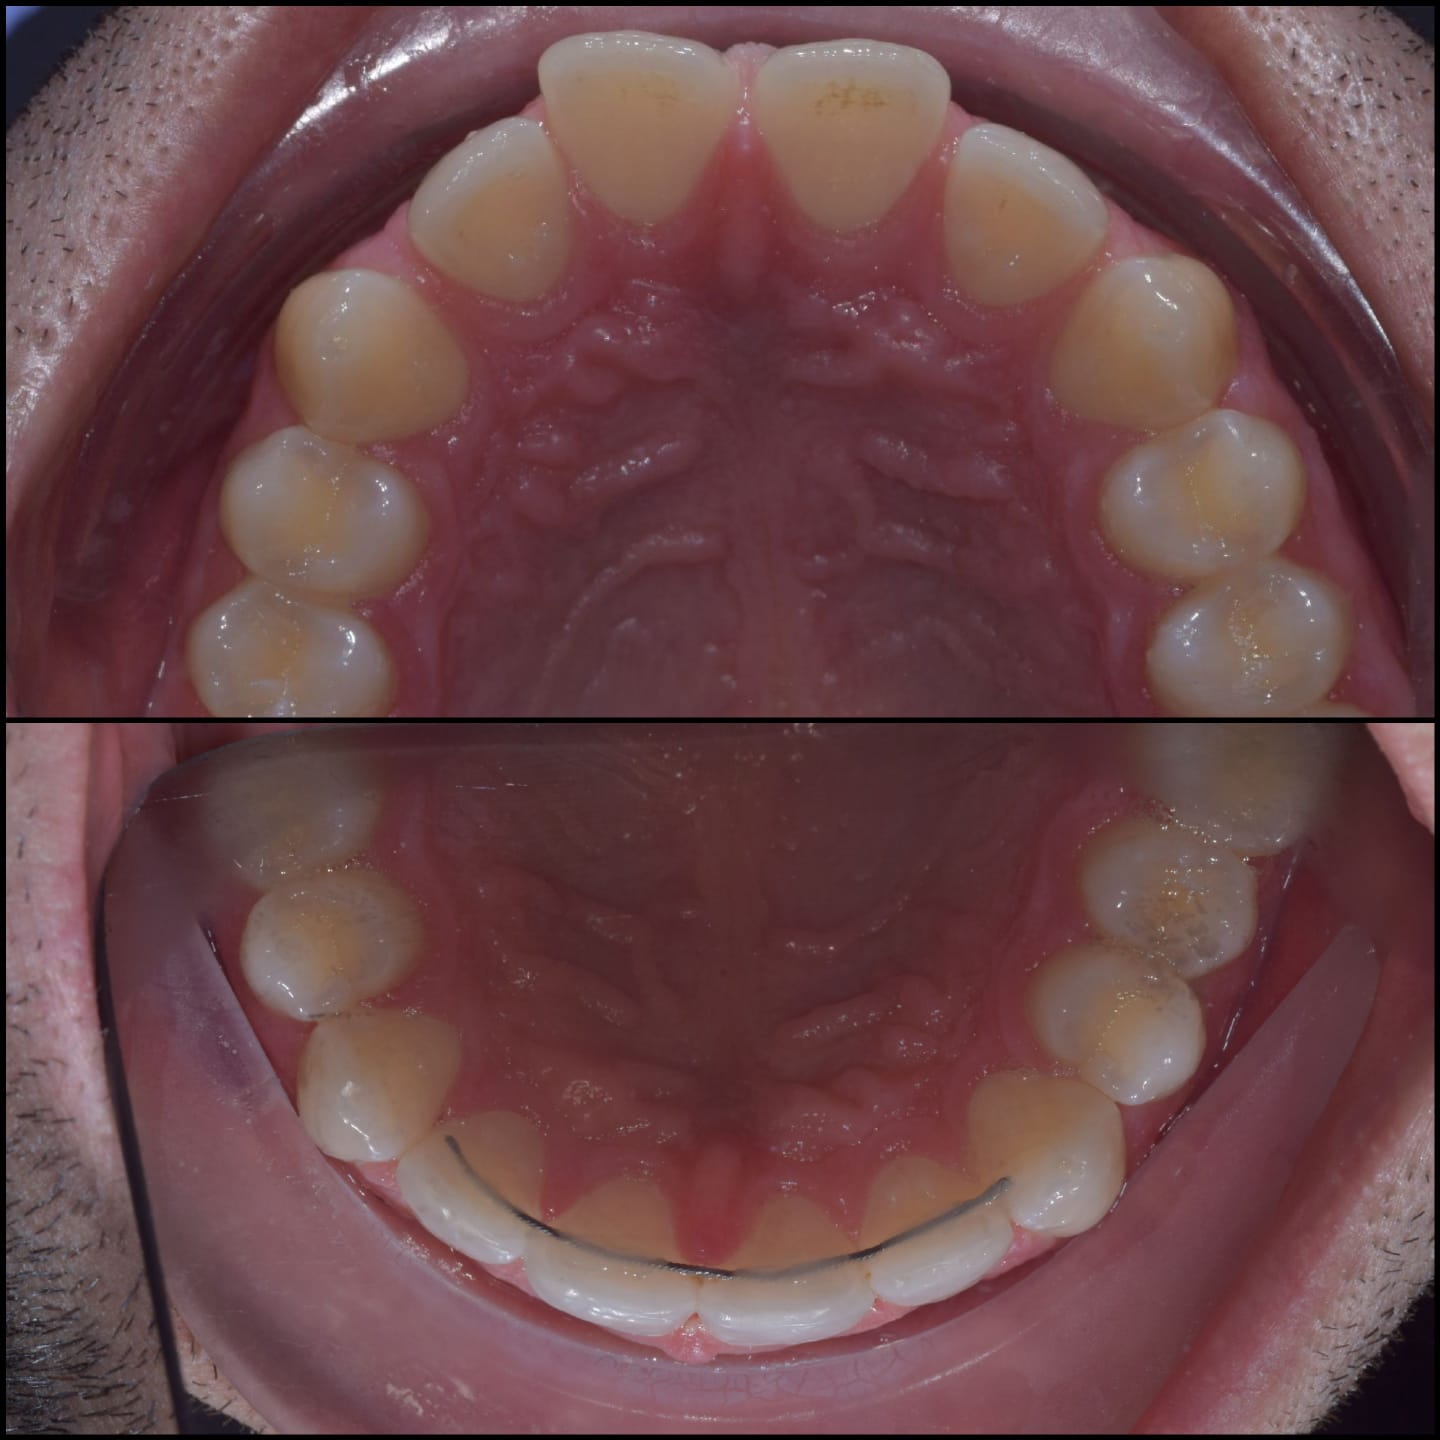

Invisalign is a clear alternative to traditional metal braces, offering a discreet and convenient way to achieve a straighter smile. Unlike traditional braces, Invisalign aligners are removable and nearly invisible, allowing you to eat, drink, and live your life without restriction. With Invisalign, you can straighten your teeth without the hassle and self-consciousness of metal braces.

Invisalign is a well-known system for straightening teeth in the most discreet way. It works by using a series of clear aligners that fit comfortably over the teeth to gently move them into the desired position over time. There are no fixed brackets or wires used, in fact, the aligners are completely removable.